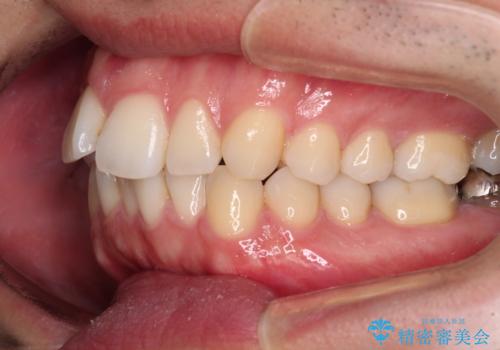

口元が出ているのが気になる。審美装置による抜歯矯正

- 口元の突出感と下の前歯のがたつきを主訴として来院された患者様です。

口元の突出感と叢生改善のため上下左右の第一小臼歯4本を抜歯し、ワイヤー装置にて矯正治療を行うこととしました。

口元の突出感もなくなり満足されました。